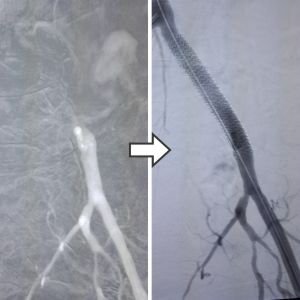

Peripheral Angioplasty

These minimally invasive but complex techniques are performed through small needle punctures and angioplasty, with Balloon/Stent/Special devices which improves blood circulation, less loss of blood and rapid recovery.